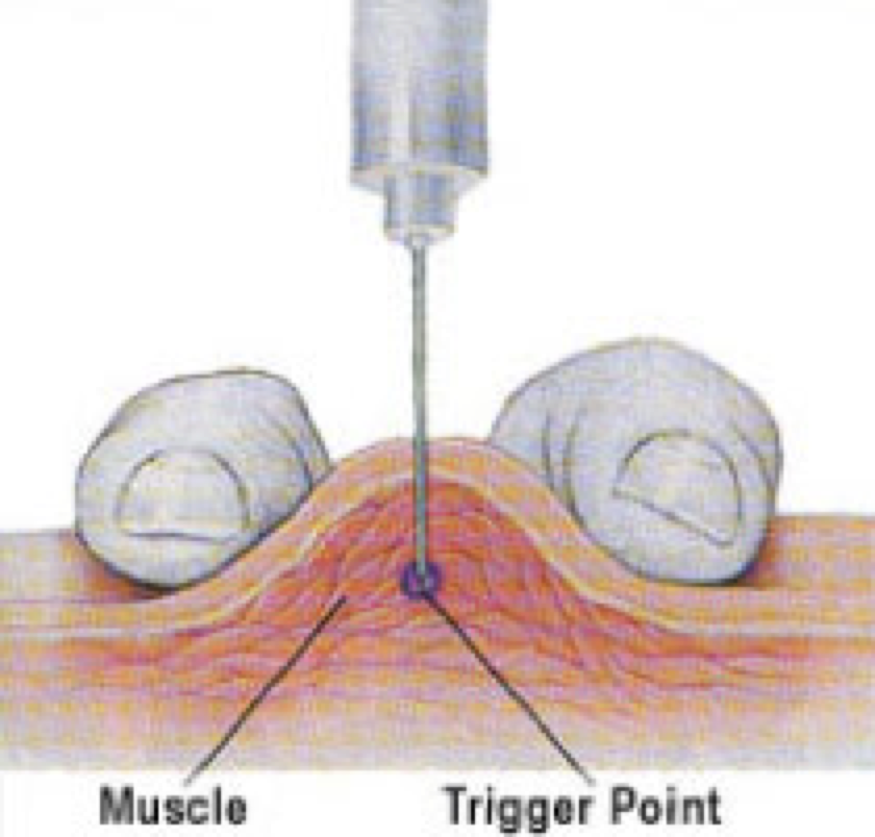

Trigger Point Dry Needling for Pain | Capital City News

Dry Needling for Plantar Fasciitis — Dry needling promotes healing by …

Trigger point Archives • Physical Health Media

Dry Needling for Plantar Fasciitis – Access Health Chiropractic Center

Pin by Kevin on Dry Needling (With images) | Trigger points, Massage …